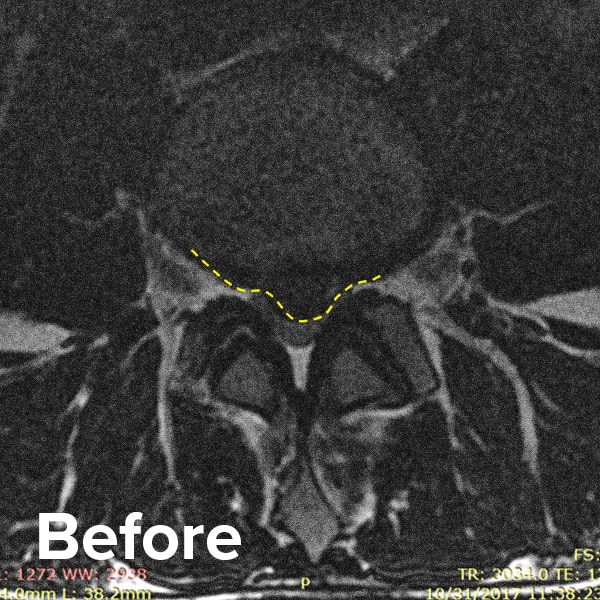

Herniated Disc MRI

Below are MRI images of the outcome of a patient who had a Regenexx PL-Disc procedure to treat a subligamentous disc herniation. After the procedure, their pain dropped quickly, and they returned to their normal activities within weeks.

Scroll the arrow to the right to see the MRI of the disc before the Regenexx PL-Disc procedure — the white/lighter area indicates damage. Scroll to the left to see the MRI of the disc after. The images are two years apart from the original treatment date.

Herniated disc before and after MRI images 1